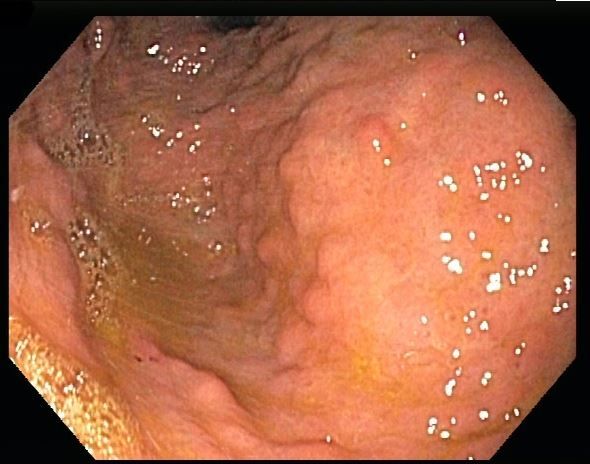

The EGD showed a Schatzki ring that was successfully dilated using an 18- to 20-mm balloon dilator. Noted in the cardia was a severely erythematous and mildly elevated gastric lesion (Figure 1). An EGD examination performed 2 years earlier showed similar findings but with mild erythema and nodular mucosa (Figure 2). Previous biopsies from that lesion had revealed mild chronic gastritis.